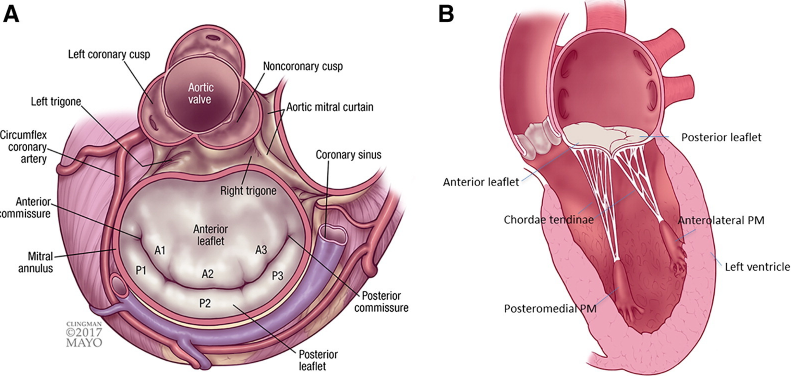

Anatomie

anatomie anatomy mitral mitrale valve valvulaire anneau mesures bilan feuillet feuillets pilier pillier piliers